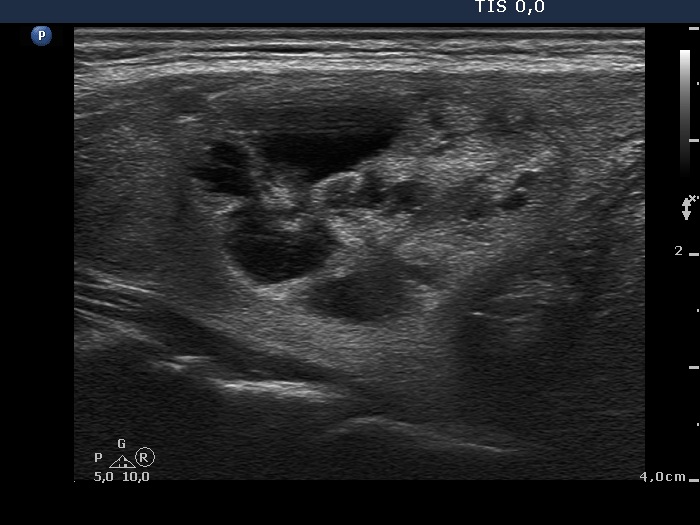

Study on 100 consecutive patients with thyroid nodule - case 068 (ultrasonographic picture 6)

Left lobe, another longitudinal view.